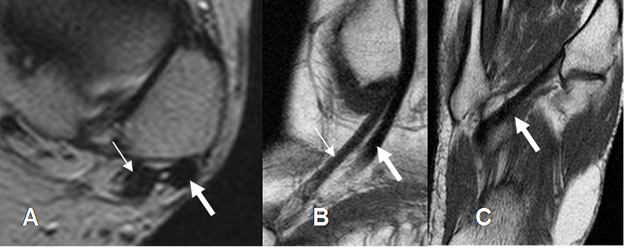

A: RM axial en T2, B: RM coronal en T2 y C: RM sagital en T1.

Fig 15. Ligamento tibiocalcáneo normal en ecografía, corte sagital.

Fig 16. Ligamento tibiocalcáneo normal.

A: RM axial y B: RM coronal en T1.

Fig 17. Ligamento calcaneoescafoideo.

A: RM axial en T1 y B: RM sagital en T2. Ligamento hipointenso normal, entre el escafoides y el calcáneo.